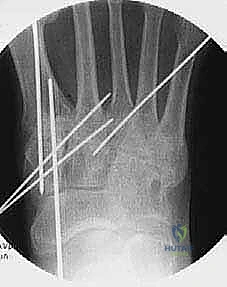

3. Temporary Stabilization: Achieving Plantigrade Alignment

Before we commit to definitive hardware, we must ensure our reduction is perfect and the foot is in a truly plantigrade position. This is where your surgical eye and tactile feedback are critical.

- "First, release any retractors and hold the foot in a reduced position. Now, palpate the forefoot. Gently press on the metatarsal heads. Ensure they are all level and the forefoot is in a plantigrade position, not dorsiflexed or plantarflexed, and without any pronation or supination."

"We'll use Kirschner wires (K-wires) and guide pins for temporary stabilization."

First TMT Joint Temporary Fixation:

- "Let's make a small stab incision over the medial aspect of the medial cuneiform, just through the skin. Use a small hemostat to dissect down to bone, carefully retracting the tibialis anterior tendon."

- "Now, we'll place our first 0.062 Kirschner wire. Aim it from the dorsal-medial aspect of the medial cuneiform, angling distally and slightly plantar, into the plantar aspect of the first metatarsal base. This K-wire should be placed where one of our final screws will go."

- "Next, place a second 0.062 K-wire. This one goes from the dorsal aspect of the first metatarsal shaft, angling proximally and slightly plantar, into the plantar aspect of the medial cuneiform. These two crossed K-wires will hold the first TMT joint securely in its reduced position."

* "Once these are in, check your fluoroscopy. AP, lateral, and oblique views. Confirm good reduction and alignment of the first ray."

- Second TMT Joint Temporary Fixation:

- "Now, let's stabilize the second metatarsal. We'll use a guide pin from our 3.0-mm cannulated screw set for this. Make a small stab incision dorsally, protecting the tibialis anterior tendon."

- "Reduce the second metatarsal to the intermediate cuneiform and ensure it's aligned with the first metatarsal base. Again, palpate the metatarsal heads to confirm they are level and plantigrade."

- "Aim the guide pin from the base of the second metatarsal, angling proximally and slightly medially, into the intermediate cuneiform. This provides axial compression and alignment."

- Third TMT Joint Temporary Fixation:

- "Finally, for the third metatarsal, make a stab incision on the lateral forefoot. Insert another guide pin from the 3.0-mm cannulated screw set."

- "Reduce the third metatarsal to the lateral cuneiform, ensuring it's in a plantigrade position relative to the second metatarsal. Aim the guide pin from the base of the third metatarsal into the lateral cuneiform."

- Final Fluoroscopic Check:

- "Before we proceed to definitive fixation, let's get a full set of intraoperative fluoroscopy images: AP, lateral, and oblique. We need to ensure adequate reduction and opposition of all arthrodesis surfaces, and that our temporary wires are in good position. Look for any gapping or malalignment. Are all metatarsal heads level on the lateral view? Is the alignment restored on the AP?"